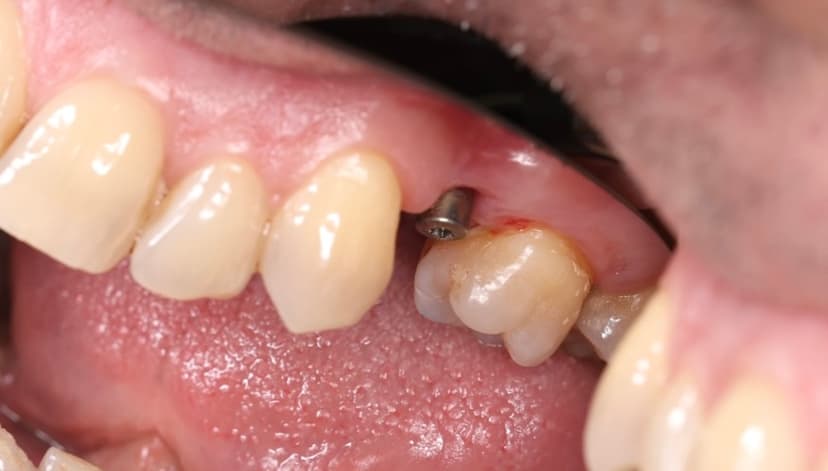

Установка абатмента временного

Установка абатмента стандартного